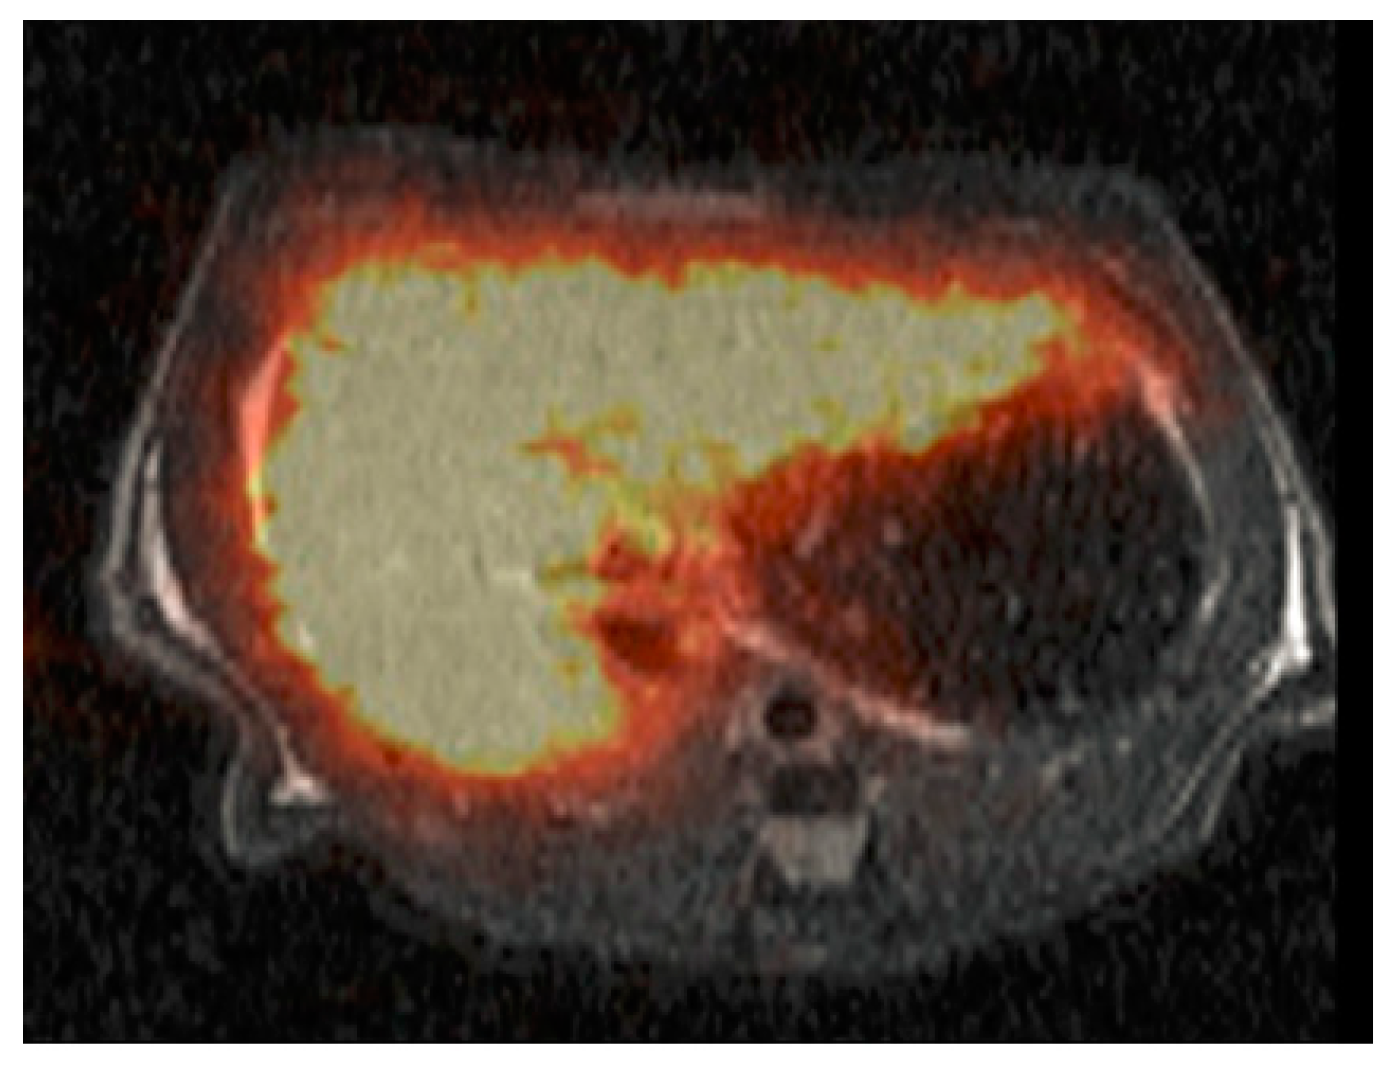

- Greiser, J.; Kuehnel, C.; Goerls, H.; Weigand, W.; Freesmeyer, M. N,1,4-tri(4-alkoxy-2-hydroxybenzyl)-DAZA: Efficient one-pot synthesis and labelling with 68Ga for PET liver imaging in ovo. Dalton Trans. 2018, 47, 9000–9007. [Google Scholar] [CrossRef]